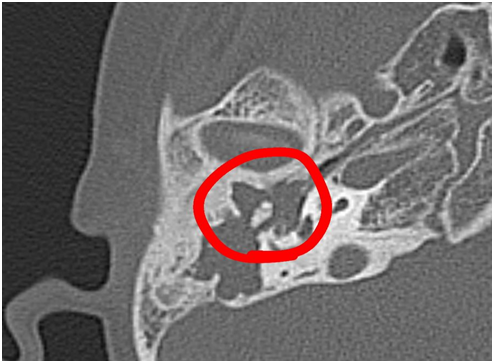

Cədvəldən göründüyü kimi, xolesteotoma ilə bağlı əməliyyat olunan xəstələrin daha çox sayı IV və V yaş qruplarındadır (20% və 44%). Xoleosteotomiya olan xəstələrdə üz kanalının köndələn kəsik sahəsinin ölçüləri artaraq, orta hesabla 2,45±0,18 mm2 təşkil edir (şək.1,2,3). Təsirə məruz qalmayan tərəfdə isə kanalın köndələn kəsik sahəsinin göstəriciləri 1,83±0,23 mm2 təşkil etmişdir ki, bu da bizim normativ dəyərlərimizlə üst-üstə düşür. Bu göstəriciləri hər iki tərəfdən müqayisə etdikdə, təsirə məruz qalan tərəfin köndələn kəsik sahəsinin ölçülərində 1,34 dəfə artım qeydə alınıb ki, bu da 74,7% təşkil etmişdir.

Bu məlumatlar digər müəlliflərin [4,5,6] belə birfikrini təsdiqləyir ki,üz kanalının təbil seqmentinin köndələn kəsik sahəsinin göstəricilərinin artması təbil damın çox nazik olmasının nəticəsidir ki, buna görə də xolesteatoma kimi həcmli proseslər asanlıqla üz kanalının divergensiyasına səbəb ola bilər. Tədqiqat işində xolesteatoma olan xəstələrdə üz kanalının ikinci dizinin bucağı ilə kanalın divergensiyası arasındakı əlaqəyə diqqət yetirilmişdir.